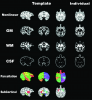

Infant Macaque MRI And DTI Templates

This is a multi-mode (T1w and DTI) brain template of monkeys during late infancy based on longitudinal data (from 6 months to 16 months), which will help spatial normalization, voxel-based and tract-based analyses in non-human primates.

3) We also made high quality template-related files, including parcellation maps, tissue probability maps, inferior cingulum mask for TBSS, and templates for each time point.